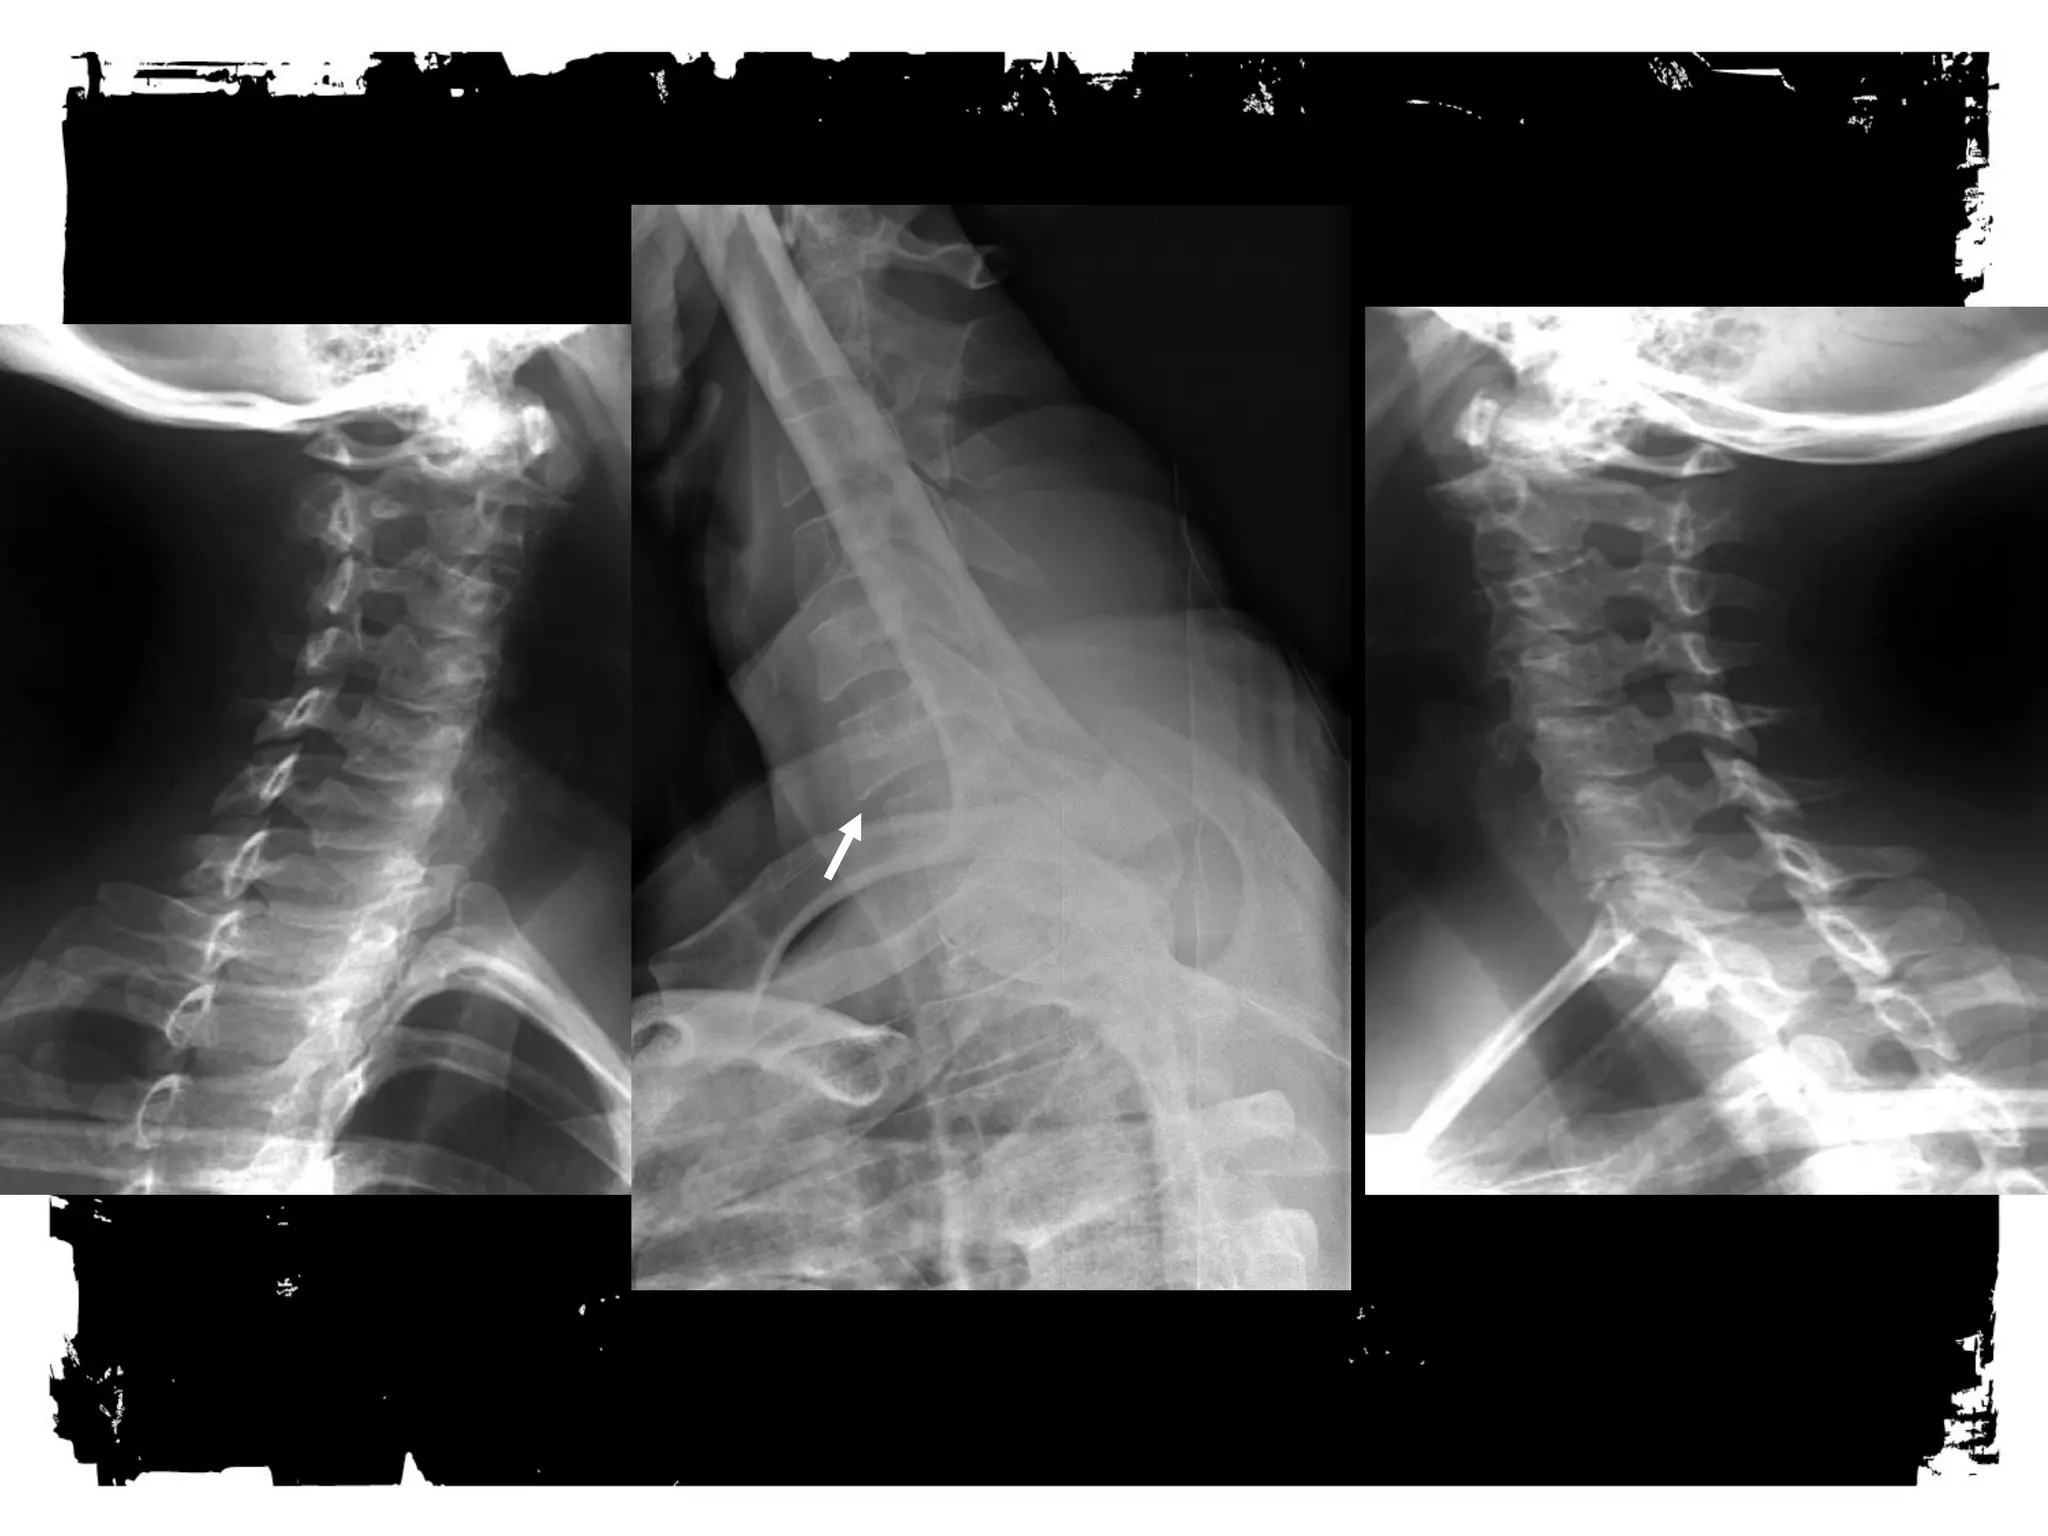

RADIOGRAPHY for primary cervical spine

screening

• Minimum standard views

– Lateral through C7

– AP

– Odontoid

Lateral View

Base of the occiput should be visualized

Junction of C7-T1 must be visualized

A swimmer’s view taken with one arm extended over

the head can be helpful

AP view

Must include the spinous processes of all the cervical

vertebrae from C2 trough T1.

Case 1

CLICK HERE TO ADD TEXT

• Unilateral Facet Dislocation

Hyperflexion + rotation

Superior facet slides over inferior facet and becomes

locked

Anterior subluxation of superior vertebral body –25%

AP diameter

Stable injury

30% with associated neurologic deficit

MRI: disk extrusion leading to cord compression

Case (2)

Bilateral Facet Dislocation

Extreme hyperflexion

Anterior dislocation of articular masses (disruption of

posterior ligament complex,PLL,disk and ALL).

Complete dislocation: dislocated vertebra anteriorly

displaced ½ of AP diameter of vertebral body

Unstable ( high incidence of cord damage)

Case (3)